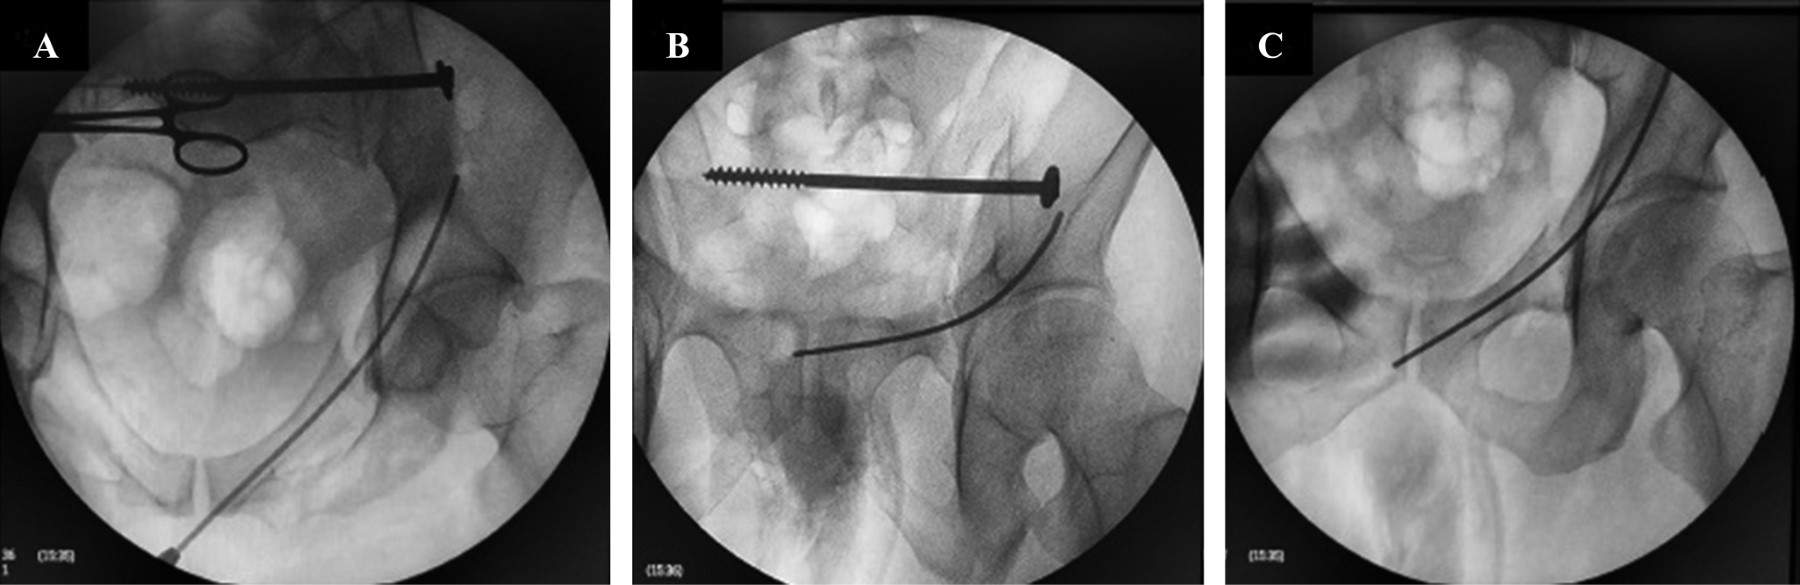

Figura 3